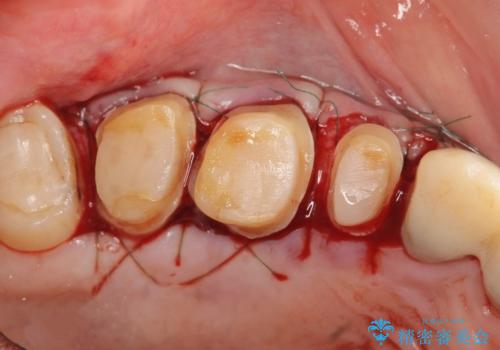

高さが短くなってしまった歯は、安定したクラウンを作るのが難しいため歯ぐきを下げる歯周外科を行ったのちに強度に優れるフルジルコニアクラウンで補綴治療を行います。

すり減ってしまった歯に対し、歯冠長延長術(歯周外科)を行うことで安定したクラウンを製作・装着することが出来ました。

- 外科手術のため、術後に出血、痛みや腫れ、違和感を伴います